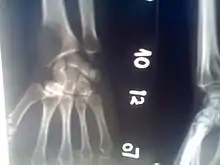

Osteolytic lesion

An osteolytic lesion (from the Greek words for "bone" (ὀστέον), and "to unbind" (λύειν)) is a softened section of a patient's bone formed as a symptom of specific diseases, including breast cancer and multiple myeloma. This softened area appears as a hole on X-ray scans due to decreased bone density, although many other diseases are associated with this symptom.[1] Osteolytic lesions can cause pain, increased risk of bone fracture, and spinal cord compression.[2] These lesions can be treated using biophosphonates or radiation, though new solutions are being tested in clinical trials.